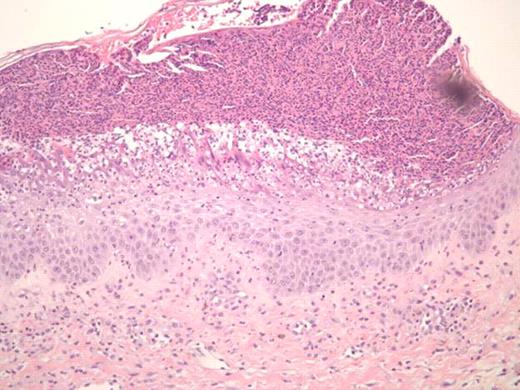

Treatment of sclerodermatous chronic graft versus host disease (cGVHD) remains a daunting challenge. Despite developments in prophylaxis for cGVHD, supportive care measures remain as the primary mode of therapy, with little evidence of treatments that reverse the process. Steroids and immunosuppressants are often ineffective, and extracorporeal photopheresis has been used with varying success. Recently, case reports have reported on the successful use of imatinib in treating sclerodermatous GVHD (Moreno-Romero et al, 2008; Leonardo Magro et al., 2009). We report a case of a 40-year-old male patient with extensive sclerodermatous cGVHD. In 2005 he underwent an unrelated stem cell transplant (SCT) for chronic myeloid leukemia. His transplant course was complicated by thrombotic thrombocytopenic purpura (TTP) associated with all standard immunosuppressive drugs (cyclosporine, tacrolimus and sirolimus). Two years later, the patient developed sclerodermatous GVHD and was given plaquenil, steroids, and photopheresis to manage this complication. Unfortunately, after months of treatment, he showed progressive disease, including increased contractures, and difficulties with inspiration. Based on case reports, and the patient's tolerance of imatinib prior to SCT, he was started on imatinib for his sclerodermatous GVHD. Within 5 days he developed generalized erythema, pustular rash, and skin sloughing (Figure 1). He was hospitalized for this severe reaction and was treated with high dose steroids after which, his symptoms began to improve. Resolution of erythema did not occur until months following initial exposure. Histological differential diagnosis included pustular psoariasis and Sneedon-Wilkinson syndrome. The skin biopsy revealed subcorneal pustular dermatosis (Figure 2). In view of this history, it is suggested that the exanthematous pustulosis was induced by imatinib in this patient. We recommend that close attention is paid to patients with cGHVD who are treated with imatinib and to intervene early in those who develop severe cutaneous reactions by stopping imatinib and starting appropriate therapy.